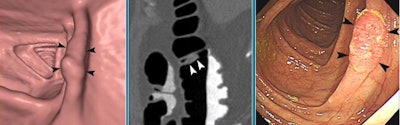

![]() |

| CTC was successful in a 51-year-old patient with a stent in the rectosigmoid junction. CTC detected a 15-mm synchronous cancer in the ascending colon. Stent can be seen in the rectosigmoid junction. |